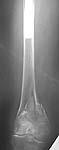

This patient generated much discussion at our institution whether a retro IMN, blade plate or LISS would be appropriate. The notch is 17 cm from the tip of the THA and I felt that the stress riser could be a problem and would feel terrible if she broke b/t the implants. The THA is so large that a blade or LISS would be difficult to get proximal purchase.

As Chip pointed out the injury was 4-7-01. No miracle, Chip, but her fixation w/ a LISS appears stable at 6 weeks w/ 0-90 knee motion. The proximal fixation is unicortical posterior to the prosthesis. Hope she continues to consolidate.

This looks good on present films - but some theoretical concerns.

Proximal femoral component support seems to be fading (stress shielding vs osteolysis) but it looks solid distally.

Doesn't the introduction of proximal plate screws set up the possibility of crevice and galvanic corrosion at a point in the femoral stem that is already at risk for cantilever mode failure?

If that is an issue and one removes LISS hardware after fx healing, what about stress risers through screw holes in the vicinity of the tip of the prosthesis?

It looks as if there are a few extra drill holes. Is that because of poor purchase in osteoporotic bone or a technical issue with the LISS procedure? I believe it can be difficult to get good fixation of a standard DHS sideplate even under direct vision in some osteoporotic femurs.